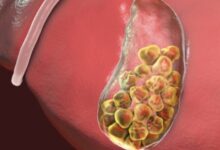

- التهاب الكبد الوبائي “ب” المزمن: في هذه الحالة تستمر مدّة العدوى بالفيروس لفترةٍ قد تتجاوز ستة أشهر، وقد لا يحدث التعافي التام منها بحيث تستمر العدوى لفتراتٍ طويلة وقد تُلازم الشخص مدى الحياة؛ إذ إنّ الجهاز المناعي لا يكون قادرًا على مُحاربتها والقضاء عليها، ومن الجدير ذكره أنّه كلما كان عمر الشخص أصغر عند إصابته بفيروس الكبد الوبائي “ب” ازداد خطر تطوّر النوع المُزمن من هذه العدوى؛ تحديدًا الأطفال ممّن هم أقلّ من 5 أعوام، ومن الجدير ذكره أنّ التهاب الكبد الوبائي “ب” المزمن قد يترتب عليه تطوّر مُضاعفات مُعينة؛ مثل تشمّع الكبد (بالإنجليزية: Cirrhosis)، أو الفشل الكبدي، أو سرطان الكبد، ومن الجدير ذكره أنّ العدوى المزمنة بفيروس الكبد الوبائي “ب” قد تستمر لعقود دون أن يتمّ تشخيصها وقد لا يتمّ الكشف عنها حتّى تتطوّر مضاعفات خطيرة تُشير إلى الإصابة بها، وعليه فإنّ التشخيص والعلاج المُبكر يلعبان دورًا في التقليل من احتمالية تطوّر المُضاعفات.

- زراعة الكبد: (بالإنجليزية: Liver transplant)، ويُلجأ لهذا الخيار في الحالات التي يُعاني فيها الفرد من تضرّر الكبد الشديد، ويستلزم الأمر وجود مُتبرع مُناسب للحالة؛ وفي معظم الحالات يتمّ الحصول على الكبد من متبرعٍ حيّ ولكنّ عددًا قليلًا من الحالات قد يتمّ بأخذ جزء من الكبد من مُتبرعين أحياء، وذلك نظرًا لقدرة الكبد على التجدّد، وخلال جراحة زراعة الكبد يقوم الطبيب بإزالة الكبد المُتضرر واستبداله بآخر صحيّ.[١٥][١٦]